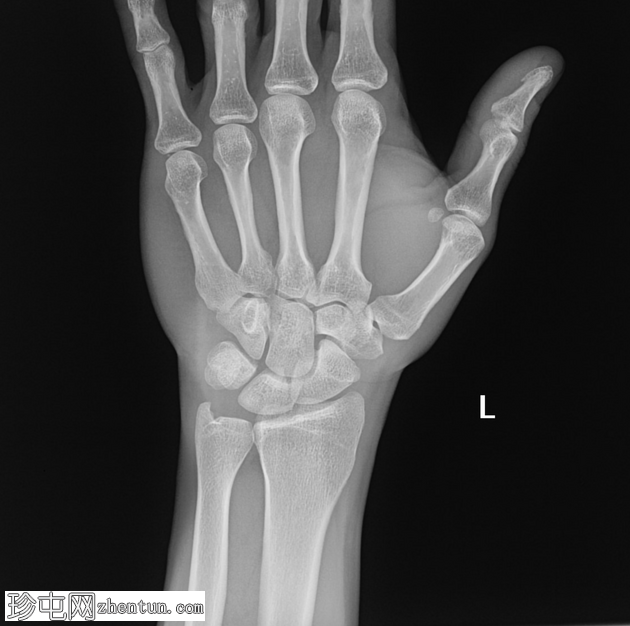

X线片

正位片

左腕关节正位和侧位X线片显示三角骨撕脱性骨折,仅在侧位片上可见,放大锐化后骨折线显示更清晰。

三角骨骨折通常由跌倒时手掌伸展着地引起。大多数骨折采用非手术治疗,即固定。三角骨骨折是继舟骨骨折之后第二常见的腕骨骨折。腕背压痛可能是患者的主要症状。放射科医生不会仅依赖X光片上的某一角度

,因为这种症状可能仅在侧位片上显现。